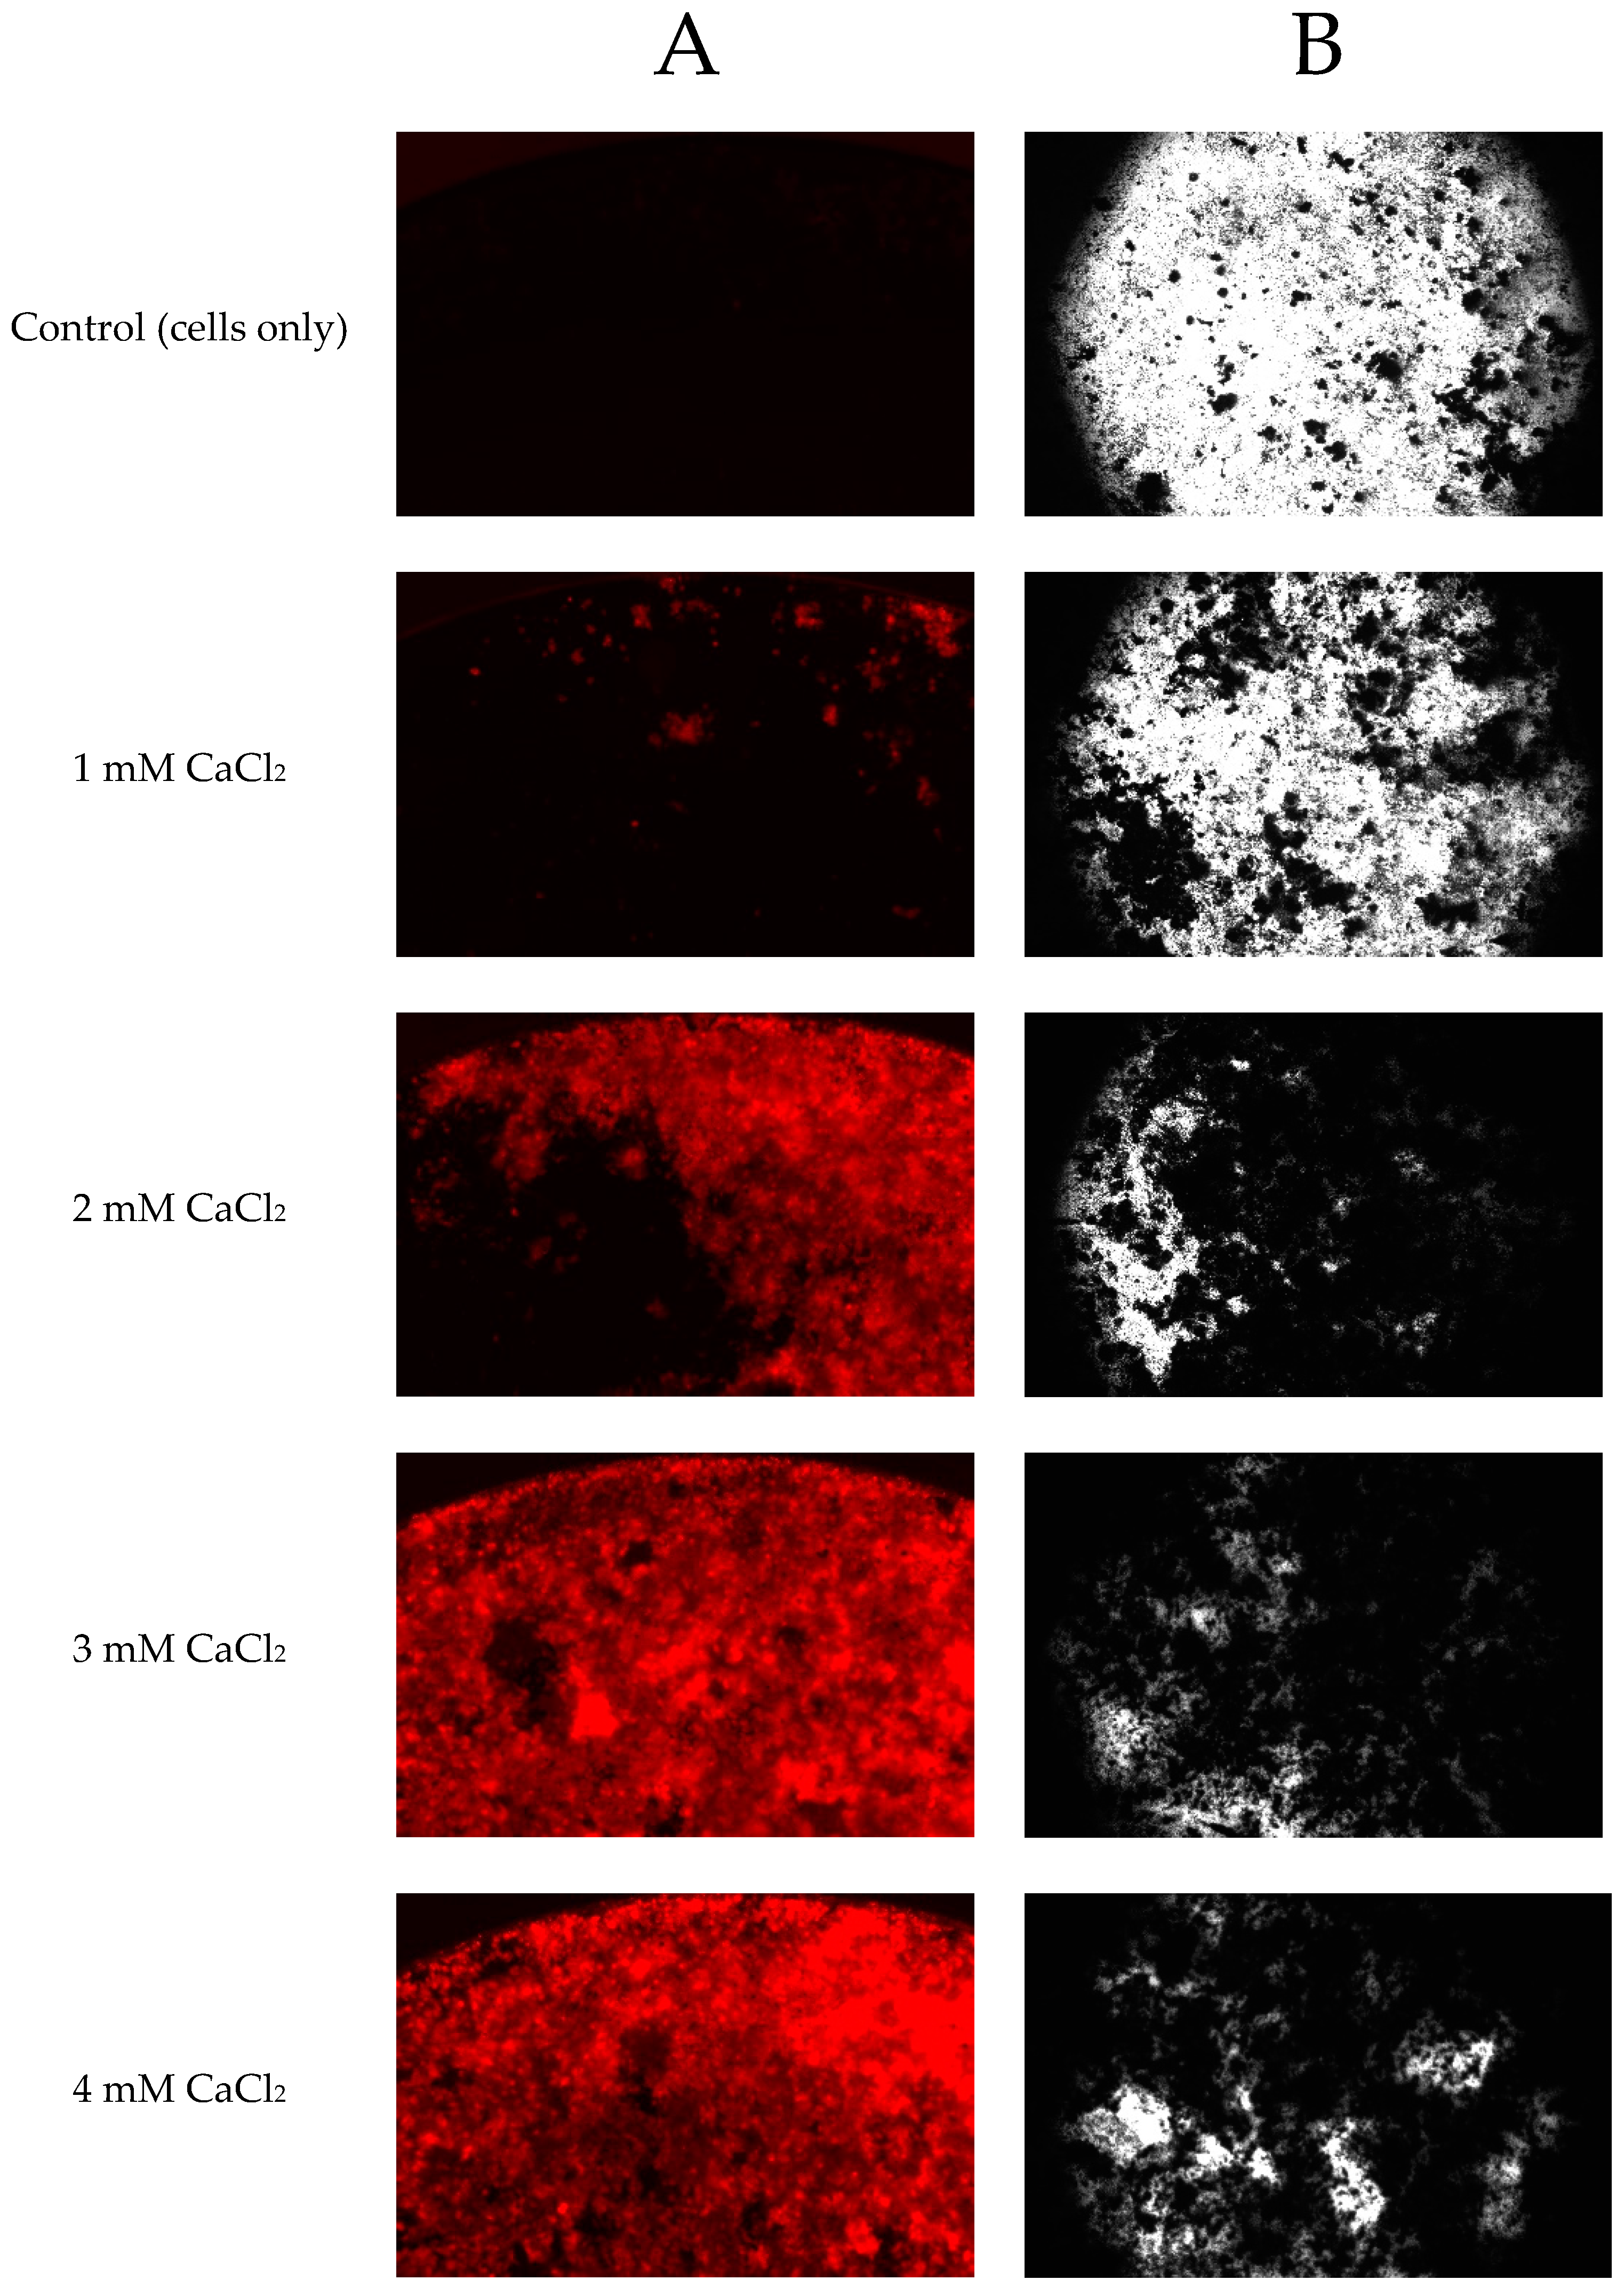

2.5. Effect of CaCl2 on Minerlization of Saos-2 Cells and the Mineralization Assay Evaluation

4.6. Determination of Mineralized Nodule Formation by Xylenol Orange Staining

4.7. Determination of Mineralized Nodule Formation by von Kossa Staining